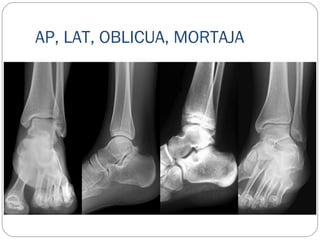

AP, LAT, OBLICUA, MORTAJA